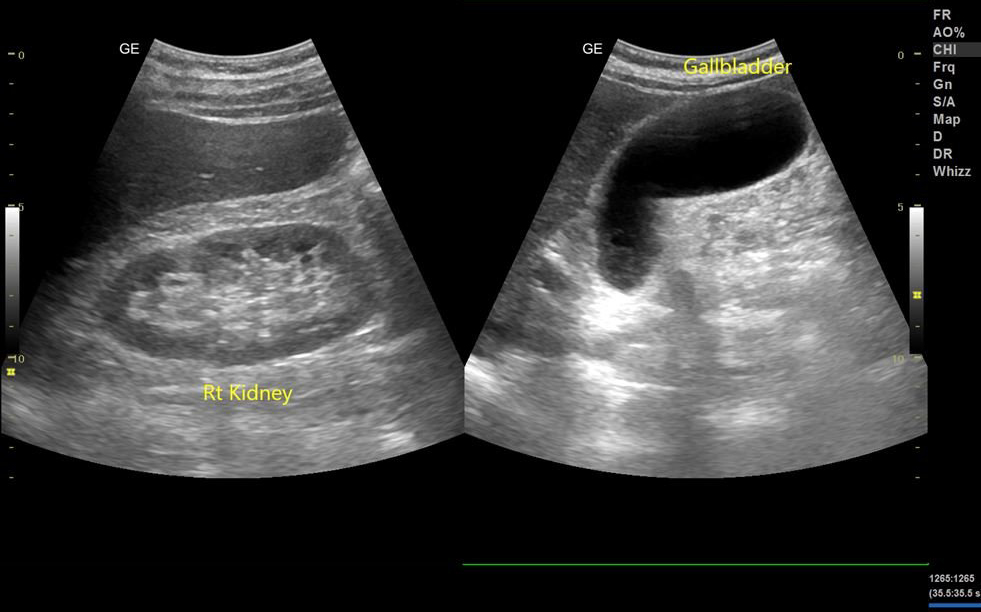

Bệnh nhân nam 70 tuổi, năm trước ghé Phòng siêu âm chẩn đoán Dr Hoa siêu âm bụng tổng quát có Phì đại tuyến tiền liệt, thể tích V# 45ml, RUV # 19ml, bệnh nhân nói có đang uống thuốc của Bs chuyên khoa. Năm nay, ghé siêu âm lại kích thước tăng V# 58ml, RUV# 127 ml, bệnh nhân bắt đầu có triệu chứng mắc tiểu không giữ được. Mình khuyên đi khám và mổ đi. Bệnh nhân phân vân và sau đó cùng gia đình quyết định mổ và nay một tuần sau mổ mọi thứ tốt đẹp. Bệnh nhân đi tiểu thông thoáng không còn khó chịu như lúc trước.